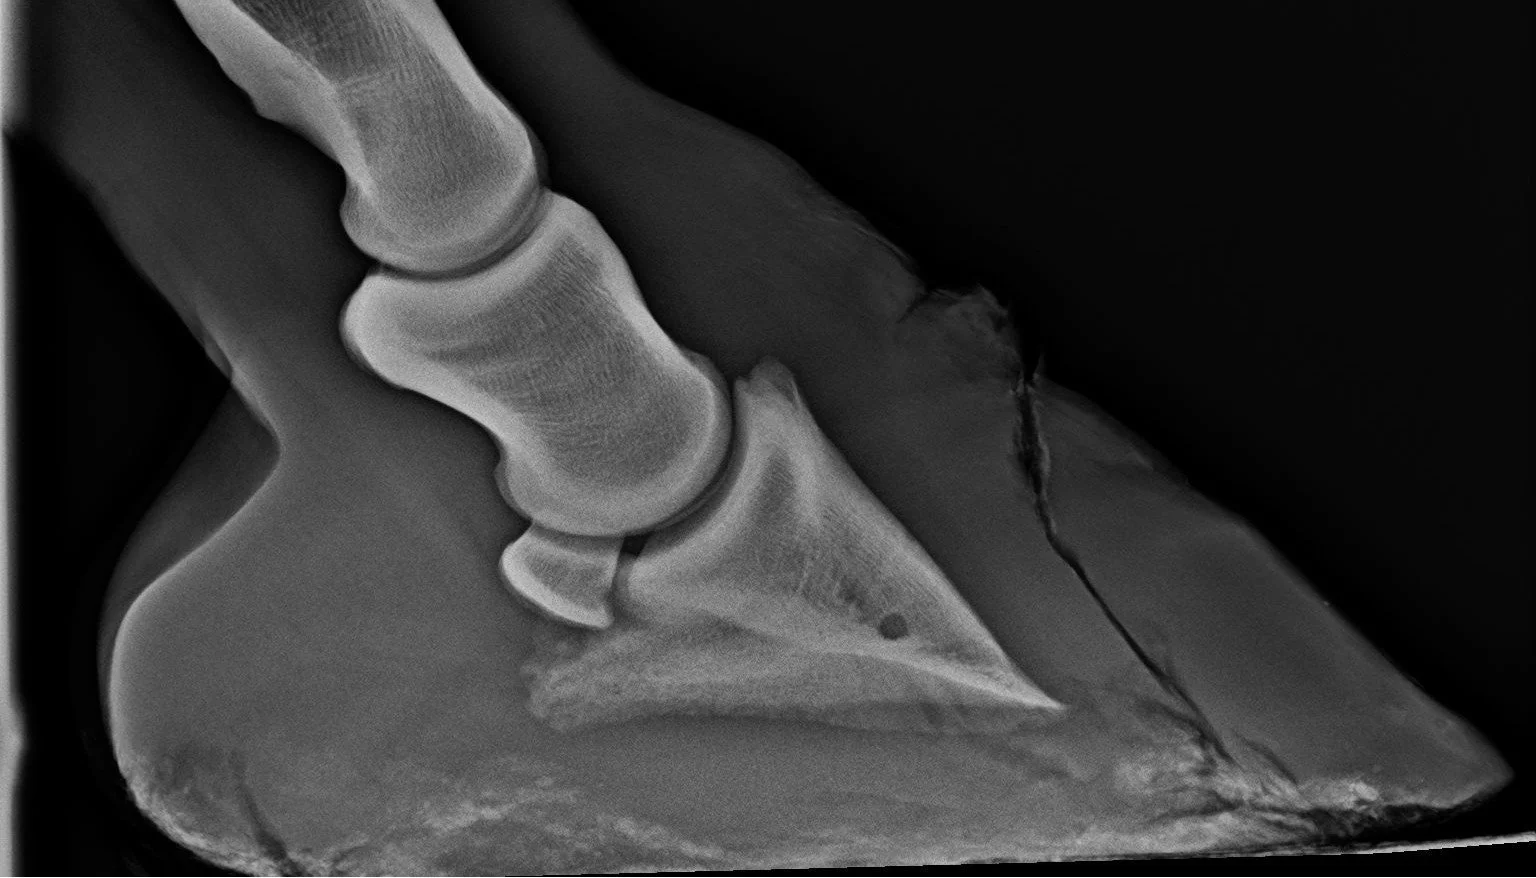

Digitales Röntgen und Ultraschall

Lahmheitsdiagnostik und -behandlung